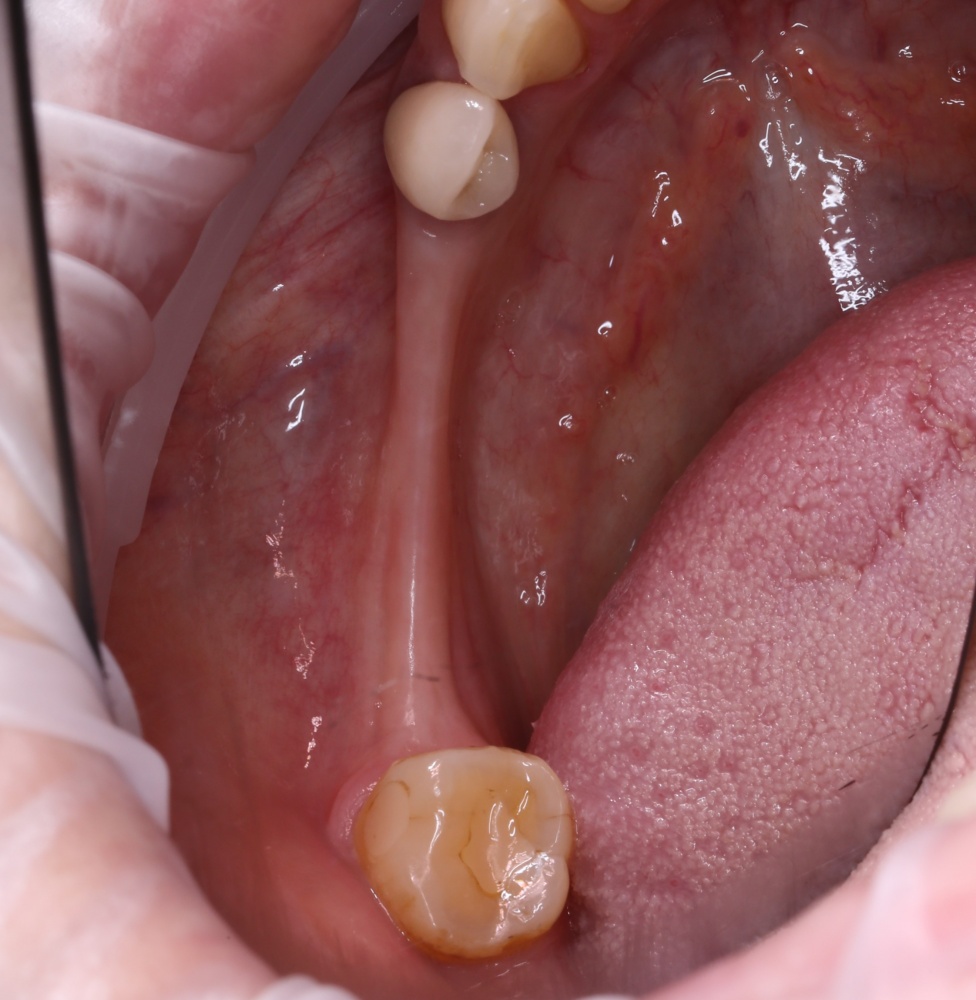

Вот клиническая картина через 4 месяца после ранее проведенной имплантации с остеопластикой:

Как видишь, коллеги из недалекой дружественной страны не осилили снятие швов. Мне это не нравится, хотя и объясняет, почему люди готовы ехать за тыщи километров ради 20-минутной операции удаления зуба мудрости.

Ну хорошо. Швы сняли. Делаем разрез. Обрати внимание, что после всех проведенных операций у нас остается очень небольшой по ширине слой жевательной слизистой оболочки: